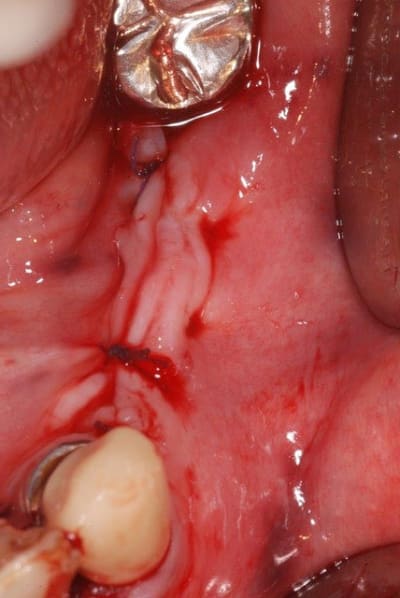

voici la nouvelle ligne muco-gingivale de la patiente.

photo 1 :ancienne lmg (quasiment sur la crête osseuse)

photo 2 : nouvelle lmg

c'est un peu long à cicatriser, on verra dans 1 à 2 mois